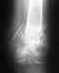

Здравствуйте. Я 25,04,06 попал в аварию, получил открытый перелом обеих костей голени.

Мне был наложен аппарат Илизарова, я с ним проходил 10 месяцев, но после того как мне его сняли, нога не выдержала и снова сломалась. Сделали еще одну операцию , накостный остеосинтез. Вот прошло уже 3 месяца но сращения как токового не видно. Посмотрите пожалуйста на снимки и дайте свое заключение.